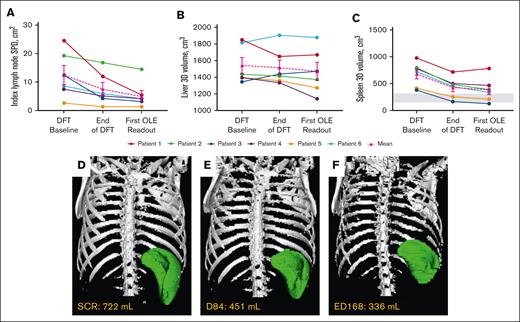

Mean index lymph node sum of product of diameters decreased 56.7%, liver volume by 4.7%, and spleen volume by 43.1% around year 1 (Table 2; Figure 3). Collectively, lymphadenopathy and splenomegaly decreased in all patients, with spleen size reaching normal range in 2 of 6 patients. Hepatomegaly was absent in 5 of 6 patients through year 6, and persistently mild in 1 patient.

Changes in lymphoproliferation parameters. (A) Individual and mean untransformed SPD of index lymph nodes. n values for all time points are 6. Reference range (≤1.5 × 1.5 cm) not shown because up to 6 lymph nodes may be counted per patient.27 (B) Individual and mean liver volumes. n values for all time points are 6. (C) Individual and mean spleen volumes. n values for all time points are 6. Gray box indicates the reference range for adults.28 Imaging used to determine lymphoproliferation for each patient at their first OLE readout was completed around year 1 (either ED168 or 252) of the OLE study. (D-F) Representative radiographic renderings of spleen volume from P6 at (D) screen of DFT (SCR), (E) end of the DFT (D84), and (F) first extension study readout (ED168) in which splenomegaly was absent. P6 had a 2-month gap in treatment between the end of part 1 and entry into the extension. D, day; ED, extension day; SCR, screen.

Changes in lymphoproliferation parameters. (A) Individual and mean untransformed SPD of index lymph nodes. n values for all time points are 6. Reference range (≤1.5 × 1.5 cm) not shown because up to 6 lymph nodes may be counted per patient.27 (B) Individual and mean liver volumes. n values for all time points are 6. (C) Individual and mean spleen volumes. n values for all time points are 6. Gray box indicates the reference range for adults.28 Imaging used to determine lymphoproliferation for each patient at their first OLE readout was completed around year 1 (either ED168 or 252) of the OLE study. (D-F) Representative radiographic renderings of spleen volume from P6 at (D) screen of DFT (SCR), (E) end of the DFT (D84), and (F) first extension study readout (ED168) in which splenomegaly was absent. P6 had a 2-month gap in treatment between the end of part 1 and entry into the extension. D, day; ED, extension day; SCR, screen.